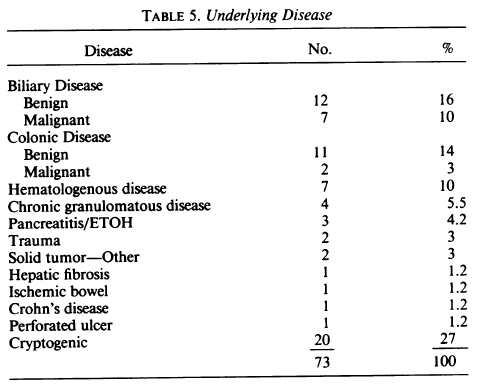

해당 간 농양에서 추출한 농에서, 항생제 감수성 테스트를 진행하였고, 결과는 다음처럼 나왔습니다.

따라서, 감수성이 있는 Ampicillin과 vancomycin, Nitrofurantoin을 사용하였습니다.

하지만, 배양 결과를 기반으로 적절한 항생제 치료를 시행하였음에도 불구하고, 환자의 임상 상태와 염증 수치는 충분히 개선되지 않았습니다. 이는 간 농양의 구조적 특성과 관련이 있습니다.

농양 내부는 fibrous capsule과 괴사 조직으로 둘러싸여 있기 때문에 항생제가 충분히 침투하기 어렵고, 따라서 약물 치료만으로는 감염원을 제거하는 데 한계가 있습니다.